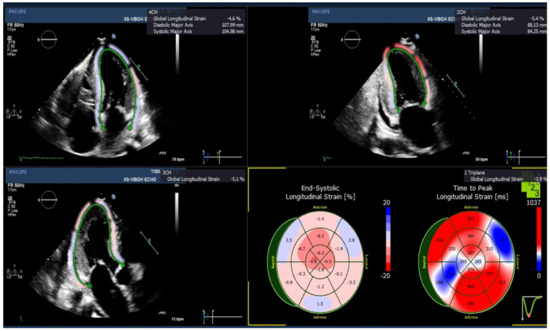

3.2. Echocardiographic Assessment of Left Ventricular (LV) Longitudinal Strains

| GLS (%), Mean (SEM) | Amyloid Patients (n = 5) | Normal Subjects (n = 8) |

| GLS, triplane | −7.96 (1.45) * | −19.44 (0.33) |

| GLS, apical four chamber | −9.10 (1.42) * | −21.51 (0.62) |

| GLS, apical two chamber | −8.12 (1.72) * | −19.35 (0.77) |

| GLS, apical three chamber | −8.0 (1.11) * | −18.45 (0.64) |